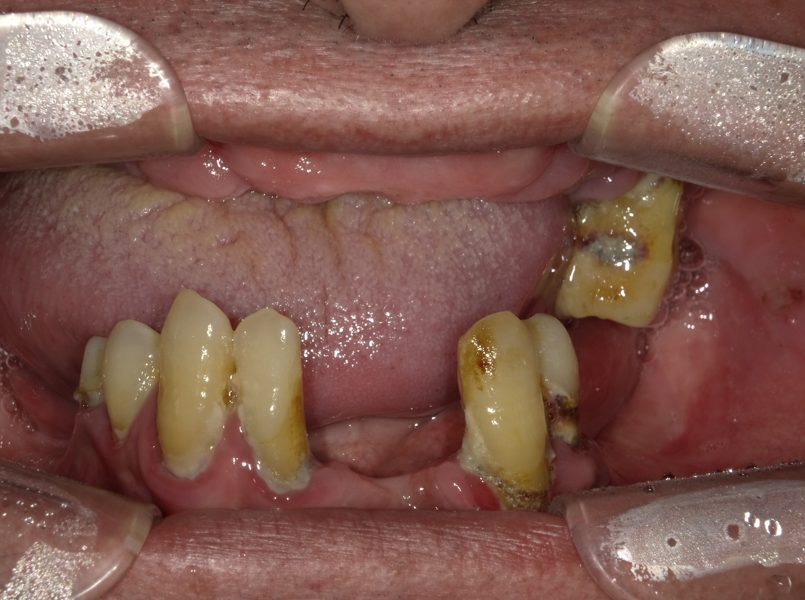

Before

治療途中

・主訴:歯がなくてうまく噛めない

・治療内容:AGCと言われている茶筒の原理を利用したセメントを用いずに審美的に優れている術者可撤式のBrを製作しました。

・院長コメント:上顎の歯槽骨の吸収も激しかったためGBR・サイナスリフトも行っております。術者可撤式といって、メンテナンス時に外して清掃、再セットが容易に行えるというメリットもあります。

・治療費(税込):3,850,000円

・治療期間・通院回数:12ヶ月・40回

・リスク:全顎治療となりますので通院回数が増えてしまいます。また骨の状態にもよりますが、骨増生とインプラント埋入手術を別に行う場合には治療期間もより長期となってしまいます。